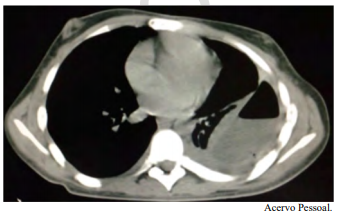

Um paciente do sexo masculino, jovem de 21 anos de idade, com diagnóstico prévio de esquizofrenia, foi internado para investigação de alteração na tomografia de tórax, conforme a imagem a seguir. A clínica apresentada era perda de peso, febre vespertina, tosse e um episódio de hemoptise. É familiar contactante de paciente com tuberculose ativa.

Com base nesse caso clínico e nos conhecimentos médicos correlatos, julgue o item a seguir.

O paciente tem indicação de pleuroscopia para descorticação pulmonar e biópsia de pleura.